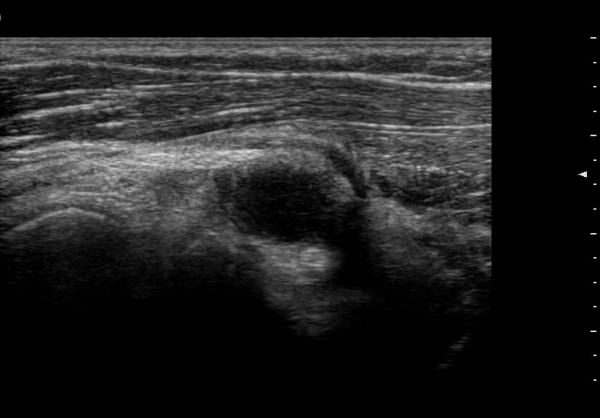

¿ä°ñ½Å°æÀÇ Èİñ°£½Å°æºÐÁö Ⱦ´Ü¸é°Ë»ç¿¡¼­ ¼ÒµÎ Ç¥Ãþ »ó¿Ï±Ù°ú »ó¿Ï¿ä°ñ±Ù »çÀÌ¿¡¼­

½Å°æ ºÐÁö°¡ Àß °üÂûµÈ´Ù(±×¸² 1).